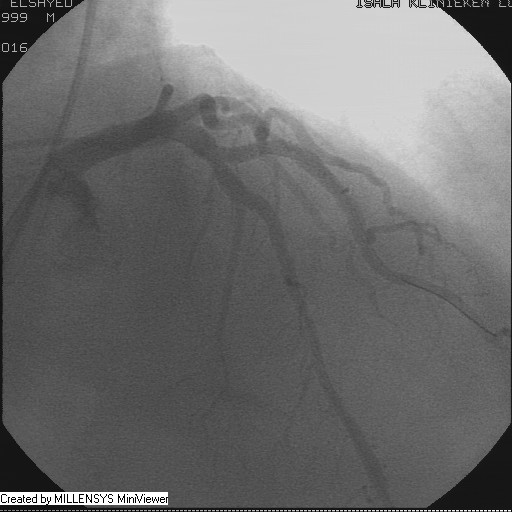

Patient transfered to Cardiac Catheterization Laboratory, coronary angiography showed atherosclerotic coronaries but without significant lesions, especially LAD that was patent with TIMI 3 flow (Figure 1- 5). Re-evaluation of the Angiography showed a small stump that can be for an occluded 1st diagonal (Figure 2a), at that level the LAD has a non-significant lesion.

Figure 3